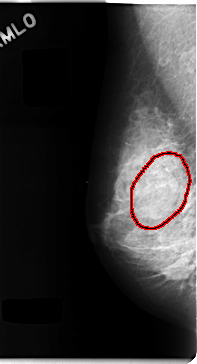

C_0107_1.RIGHT_MLO

FILE: C_0107_1.RIGHT_MLO.OVERLAY

TOTAL_ABNORMALITIES 1

ABNORMALITY 1

LESION_TYPE MASS SHAPE OVAL MARGINS CIRCUMSCRIBED

ASSESSMENT 3

SUBTLETY 4

PATHOLOGY BENIGN

TOTAL_OUTLINES 1

BOUNDARY